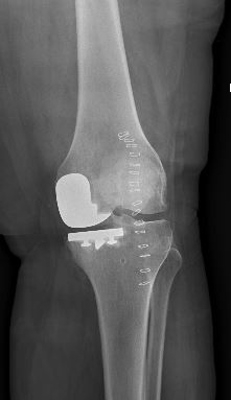

Example X-Ray Images

Partial Knee Replacement